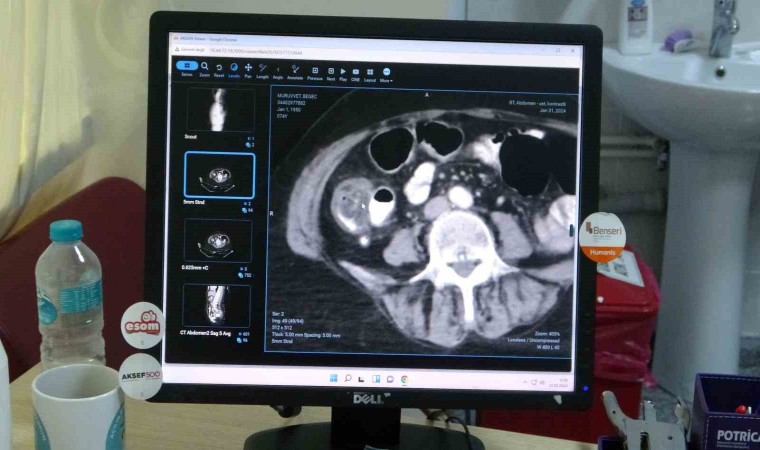

Dünya Sağlık Örgütü’nün verilerine göre, kalın bağırsak kanserinin kalp damar hastalıklarından sonra en fazla ölümlere neden olan bir hastalık çeşidi olduğuna dikkat çeken Genel Cerrahi ve Gastroenteroloji Cerrahisi Uzmanı Dr. Mehmet Güzel, “Kalın bağırsak kanseri kalp damar hastalıklarından sonra Dünya Sağlık Örgütü’nün verilerine göre en fazla ölüm nedeni olarak yer almaktadır. Kanser hastalıkları arasında ise Akciğer, meme, prostat kanserinde sonra dördündü sıklıkta görülmektedir. Türkiye’de 2022 verilerine göre yılda 22 bin kişiye kolon kanseri tanısı konulmaktadır bunların yaklaşık 12 bini vefat etmektedir” dedi.

Hastalığının belirtileri hakkında bilgiler paylaşan Güzel, “Kalın bağırsak hastalığında belirtileri ise tuvalet alışkanlıkları çok önemli yer tutmaktadır. Eğer tuvalet alışkanlığında değişiklik söz konusu ise uzun süre kabızlık ve kana ve kilo kaybı söz konusu ise kalın bağırsak tümörü açısından şüpheli duruma gelmişti. Bu noktada kolonoskopi yapmakta fayda vardır” ifadelerini kullandı.

Kalın bağırsak kanserinin erkeklerde daha fazla göründüğünü aktaran Gül, “Kalın bağırsak kanserinden korunmaların yolları için ise egzersiz, D ve B vitamini, kalsiyum içeren gıdaların tüketilmesi kırmızı etli ürünlerden uzak durulması gerekiyor. Bitkisel ürünlere ağırlık vermek lazım. Kalın bağırsak kanseri şüphesi olanlar kesinlikle kolonoskopi yaptırmalıdır. Kalın bağırsak kanseri erkeklerde biraz daha fazla görülmektedir” diye konuştu.